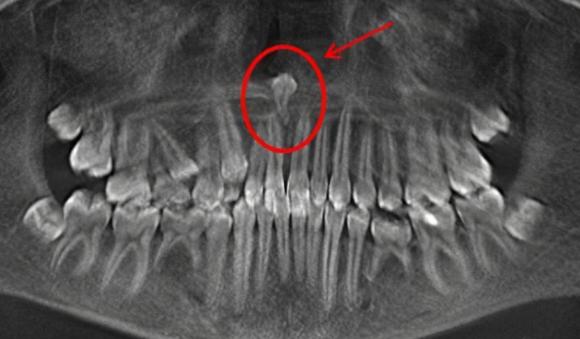

一、可能是多生牙一般我们的恒牙是28~32颗,乳牙20颗,额外长的牙就是多生牙。

有的埋在骨头里,也有长出来的。

如果多生牙不仅长了,还占了正常牙的地儿,被挤走的正常牙就只好自寻出路了,靠近嘴唇这侧还挺宽敞,那就往这里长吧,小歪牙就出现了。